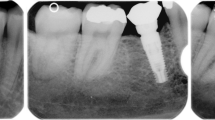

Digital periapical radiographs were made at implant placement (T0) and abutment selection phase (Ta) and were used to assess radiographical peri-implant alterations during the osseointegration period (4 to 6 months). Radiographs were performed with an intraoral X-ray positioning device by a single, previously calibrated, operator to ensure standardization. The digital files were then imported into software (ImageJ 1.47v, NIH, USA) to assess the differences in the distance between the implant platform and the alveolar bone crest in T0 and Ta. The distances were measured both in mesial and distal areas (Fig. 1) and were the average value was reported according to each implant [11]. All radiographs were assessed by a single researcher who was previously calibrated and blinded to the interventions.

No differences were observed when LLLT, and control groups were compared with ISQ difference (Ta–T0) (p=0.598) or radiographical peri-implant alterations (p=0.531). However, when comparison was made between LLLT and control groups at abutment selection phase (Ta), a statistically significant difference was found (p=0.030), where LLLT group presented an average distance of 1.95mm between the implant platform to the radiographic bone crest. All ISQ and implant platforms to bone crest distance values according to each intervention are presented in Tables 2 and 3, respectively.

The peri-implant marginal bone and its alterations are another very important and reliable outcome in regard to implant success and survival [24]. It has been reported that a successful implant would not have a marginal bone loss greater than 1.5 mm in the first year [25], and in the subsequent years, it should be restricted to 0.2 mm per year [26]. As the osseointegration depends on the migration of osteogenic cells to the peri-implant surrounding area [27], it could be also hypothesized that LLLT could stimulate the early stages of bone formation. Our findings comparing the radiographical images at T0 and Ta did not present statistically significant differences (0.531). However, a statistically significant difference was observed at abutment selection phase for LLLT group (p=0.030), presenting an average distance of 1.95mm between the implant platform to the radiographic bone crest, similar to the recommended by the implant manufacturer (2mm), although this bone loss was in agreement with the biological process of remodeling (Table 3).